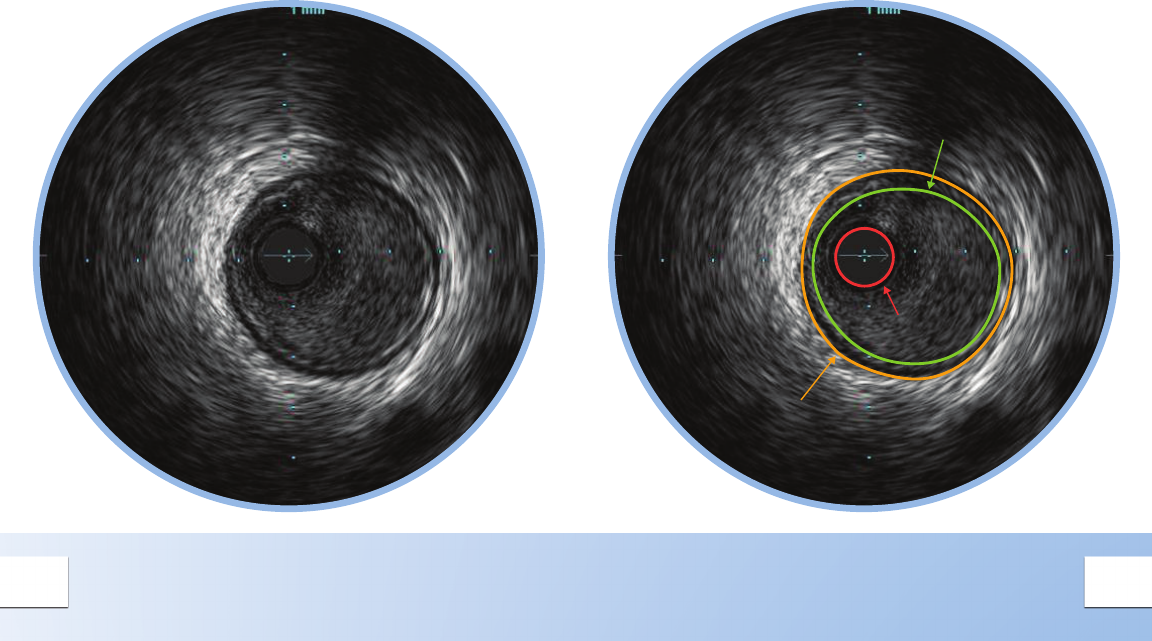

NORMAL VESSEL

In a normal vessel, the lumen border is almost

indistinguishable from the vessel border. While

IVUS allows visualization of vessel and lumen,

angiograms only provide a shadow of the

lumen. In patients with diffuse disease, relying

on the angiogram alone can potentially lead to

underestimation of stenosis.

The lumen border is drawn inside the intima

or plaque.

The intimal layer is normally not seen unless it has

begun to thicken.

The catheter mask (red area) indicates the location

of the ultrasound transducer.

The media is the dark band between the adventitia

and the intima.